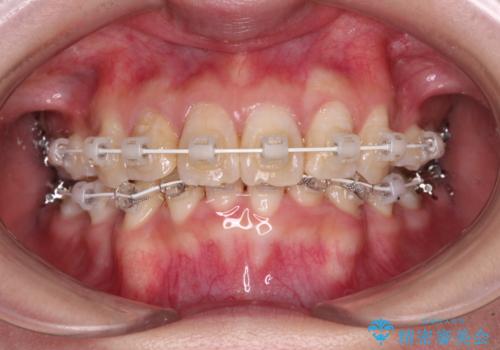

- 矯正装置

- 審美装置

咬み合わせが深く、そのままでは上顎の抜歯スペースが閉じきらない可能性があったため、治療初期から深い咬み合わせを改善させるように試みました。

実際にはなかなか改善されず、当初予定よりも治療期間がやや長期化してしまいました。